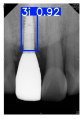

| Image Resolution = 825 × 1200 | ||||

| Test Image 1–4 | ![]() | ![]() | ![]() | ![]() |

| Accuracy | 94.13% | 95.29% | 92.88% | 91.80% |

| Recall | 96.71% | 94.03% | 93.88% | 92.15% |

| Model reference time | 6.57 ms | 7.08 ms | 7.12 ms | 6.43 ms |

| Dentists’ average diagnostic time | 2.78 s | 4.55 s | 7.78 s | 7.23 s |